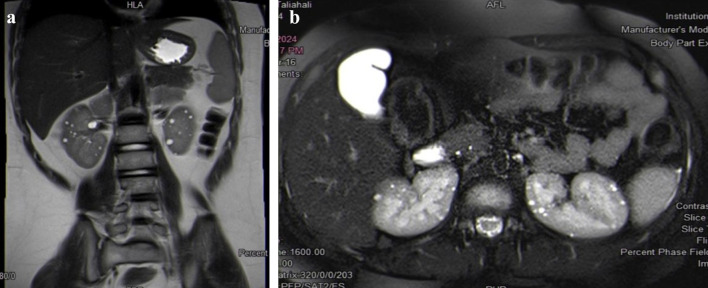

结节性硬化症(TSC)是一种常染色体显性遗传的神经皮肤疾病。由于错构瘤在不同器官中形成,其特点是多系统受累。TSC2基因突变是该疾病最常见的原因,与TSC1基因突变相比,与更严重的神经系统症状相关。然而,在我们的病例中,我们报告了一名2- 5个月大的女孩在TSC2基因外显子37侧剪接位点检测到的罕见突变。她在1个月大时出现全身异常的肢体运动。对遗传数据库的回顾显示,在文献中没有关于该基因的先前报告。她的诊断经TCS基因面板证实。后来,她发展为肾细胞癌。这些病例由一个多学科团队管理,包括一名儿科医生、一名儿科神经科医生、一名儿科心脏病专家、一名儿科血液肿瘤学专家和一名儿科外科专家。TSC患儿的总体预后是可变的,取决于症状的严重程度,尤其是神经系统表现。

Tuberous sclerosis complex (TSC) is a neurocutaneous disorder inherited in autosomal dominant manner. It is characterized by multisystem involvement due to the formation of hamartomas in different organs. TSC2 gene mutations are the most common cause of the disease and are associated with more severe neurological symptoms compared to TSC1 gene mutations. However, in our case, we are reporting a rare mutation detected at the flanking splice site of exon 37 in the TSC2 gene in a 2-year-5-month-old girl. She presented to the emergency department at the age of 1 month with generalized abnormal body movements. A review of genetic databases revealed no prior reports of this gene in the literature. Her diagnosis was confirmed by gene panel for TCS. Later, she developed renal cell carcinoma. Such cases are managed by a multidisciplinary team including a pediatrician, a pediatric neurologist, a pediatric cardiologist, a pediatric hematology-oncology specialist, and specialist in pediatric surgery. The overall prognosis of children with TSC is variable and dependent on the severity of symptoms, especially neurologic manifestations.